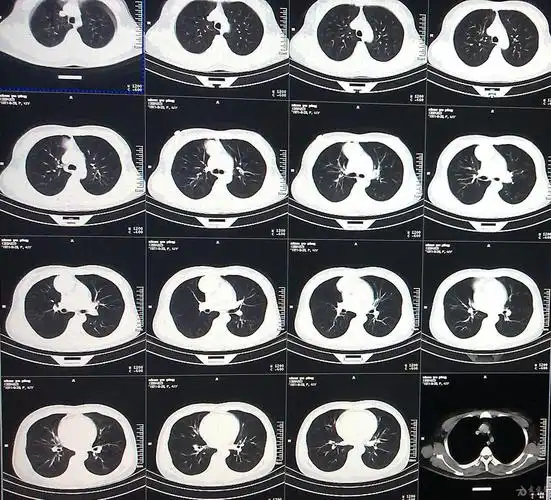

外院ct平扫

胸部ct平扫示左下肺占位肺癌

女性,无任何自觉症状,体检肺ct平扫 增强